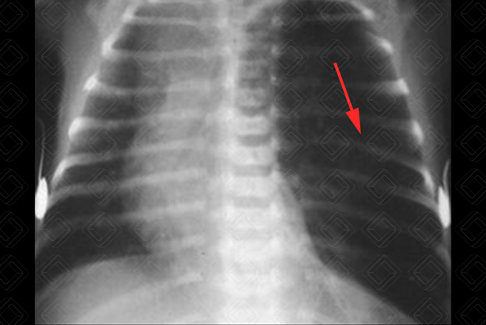

Texto alternativo para a imagem Figura 1. Créditos: Dra. Elazir Mota - Rio de Janeiro/RJ

Descrição da figura 1: Trata-se de um caso de hipertransparência pulmonar unilateral na radiografia de tórax. Observe que a transparência pulmonar esquerda é maior que a direita (ou seja, o pulmão esquerdo encontra-se mais “preto” que o contralateral) – seta vermelha. Foram afastadas as outras possibilidades diagnósticas e confirmada a síndrome de Poland.

• Causas extrapulmonares: Fatores técnicos, anomalias/alterações da parede torácica: mastectomia, síndrome de Poland (figura 1) , escoliose grave/acentuada; alterações pleurais: pneumotórax;